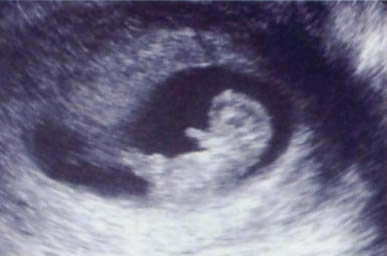

命のめばえ

超音波検査器機は、ME室(陣痛室)に1台あり、入院中の妊婦さんの腹部超音波検査に使用しています。また、分娩室の1台は、分娩時の母体・胎児の急変の際や、県内の各施設から搬送される救急母体搬送の対応の際に使用しています。